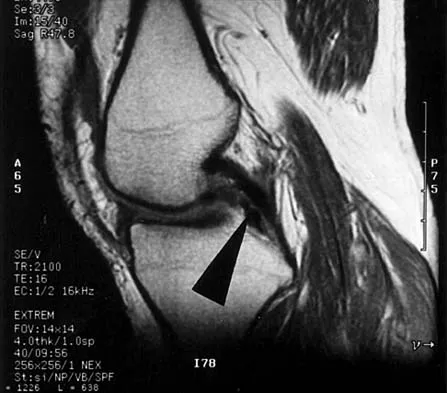

Question 1:

A 13-year-old boy has pain and a firm mass in his left knee. A radiograph and MRI scan are shown in Figures 2a and 2b, and a biopsy specimen is shown in Figure 2c. Based on these findings, what is the most likely diagnosis?

Correct Answer: Osteosarcoma

Explanation:

The most likely diagnosis is osteosarcoma. The imaging studies show an aggressive primary tumor of bone, and the histology slide shows a typical chondroblastic osteosarcoma, with osteoid deposited along the surface of bone trabeculae. Ewing's sarcoma histologically consists of small round blue cells. Osteochondroma and periosteal chondroma can occur near the knee but have different radiographic and histologic patterns. Chondrosarcoma rarely occurs in children. Simon M, Springfield D, et al: Osteogenic sarcoma: Surgery for Bone and Soft Tissue Tumors. Philadelphia, PA, Lippincott Raven, 1998, p 267.